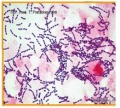

链球菌